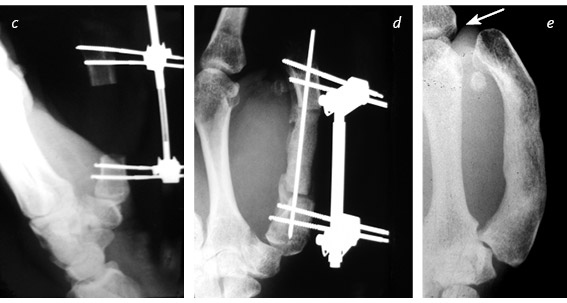

Кистевые хирурги [37] все это знают и при необходимости будут трудиться ночь напролет, лишь бы вернуть поврежденный палец на место. Даже полностью отделенный большой палец можно успешно приживить – реплантировать. Его чувствительность, подвижность и сила никогда полностью не восстановятся, но так, безусловно, лучше, чем вообще без пальца. Если восстановить или приживить эту важнейшую часть кисти невозможно, ее реконструируют. Существует три основные методики, которые я условно называю «упросить», «одолжить» и «украсть». В первом случае хирург и пациент как бы упрашивают обрубок большого пальца вырасти в длину. С обоих концов оставшейся кости хирург вставляет поперечные стальные шпильки, прикрепляет эти шпильки к стальной раме и разрезает кость между ними. Пациент каждый час поворачивает небольшую ручку этого приспособления, напоминающего аппарат Илизарова, и по чуть-чуть увеличивает промежуток между фрагментами кости. Процедура длится от шести до восьми недель. Кость и окружающие ее мышцы, сухожилия, нервы и кожа едва ли понимают, что их растягивают: для них это просто какой-то очень быстрый рост, и им надо успеть. Когда большой палец вновь обретает рабочую длину, хирург заполняет промежуток костным трансплантатом. Преимущество такого способа удлинения в том, что не приходится ничего «одалживать» или «красть». Однако не все так радужно: ноготь и отсутствующие суставы большого пальца уже не вернуть. Другие четыре пальца – указательный, средний, безымянный и мизинец – работают аналогично друг другу, и потеря одного из них имеет гораздо меньшие последствия, чем потеря большого пальца. На этом и основана вторая методика реконструкции большого пальца. Как вы думаете, что приходит в голову хирургу, если незаменимого большого пальца не хватает, а рядом расположились четыре его недостаточно занятых дружка? Разумеется, позаимствовать один из них! Обычно выбирают самый близкий – указательный. Хирург укорачивает его и разворачивает в положение большого. Эта процедура сложнее, чем удлинение остатка пальца, рука становится четырехпалой, зато новый большой палец будет иметь ноготь, и восстановление пройдет быстрее. ![]() ![]() В данном случае культя большого пальца была постепенно увеличена до длины, достаточной, чтобы сжимать и хватать. До лечения большой палец заметно короче – для сравнения стрелкой отмечен первый сустав указательного пальца (a). Во время первой операции врач ставит дистракционное устройство, разрезает кость и осторожно раздвигает ее концы (b). Расстояние между фрагментами кости постепенно увеличивают (на это уходит от шести до восьми недель), наращивают кожу, сухожилия, нервы и кровеносные сосуды (c). После этого в расширенный промежуток кости пересаживают трансплантат из бедра (d). Когда пересаженная кость заживает, работоспособность пальца восстанавливается, и аппарат снимают. Стрелкой показана новая длина по сравнению с исходным состоянием (e) ![]() Реконструкция большого пальца путем укорачивания и разворота указательного пальца: состояние до операции (a) и после нее (b, c) Бывает, что на одной кисти руки не хватает сразу нескольких пальцев или пациенту нужны все пальцы. В этих случаях «пригласить соседа» не получится. Если не удается «уговорить» культю вырасти, хирург может прибегнуть к «краже». Жертвой становится стопа. Большие пальцы ноги по форме почти идентичны своим собратьям на руках, поэтому именно они чаще всего идут в дело – вот только место преступления выглядит довольно неприглядно. Если похитить второй палец ноги, замена из него получится совсем тощая, зато ступня будет иметь аккуратные очертания. Такой вариант обычно выбирают в странах, где в помещении принято снимать обувь. На способность ходить и бегать отсутствие первого или второго пальца ноги почти не влияет. ![]() У этого пациента большим пальцем ноги заменили большой палец левой руки, утраченный в результате травмы. Стопа после операции полностью сохранила функциональность Операция по пересадке пальца с ноги на руку длится от пяти до десяти часов и требует прекрасного владения навыками микрохирургии. Хирург определяет нервы, артерии, вены и сухожилия пальца стопы, изолирует их и отрезает вместе с костью. Ампутированный палец переносят на руку и стыкуют аналогичные ткани между собой. Хирург обычно крепит кость пересаженного пальца к оставшейся в руке кости с помощью стальных штырей. Диаметр кровеносных сосудов – от полутора до трех миллиметров: их необходимо точно соединить практически невидимыми швами, ведь кровь должна двигаться по сосудам, не просачиваясь наружу. Когда кровообращение возобновится, концы кости будут спокойно заживать, не понимая, что стопа перепуталась с кистью руки. Пройдут месяцы, в пересаженный палец врастут новые нервные волокна, и чувствительность восстановится. По-английски получившуюся комбинацию иногда называют thoe [38]. * * * Помните? В период своего зарождения в XVIII веке ортопедия в основном занималась детьми. Доктора лечили деформации скелета, возникшие вследствие перенесенных заболеваний (туберкулеза, полиомиелита и рахита), исключительно неоперативными методами. Со временем эти болезни ушли в прошлое, появилась общая анестезия, возросли требования к стерильности, операции стали значительно безопаснее, а методы лечения усложнились. Один из таких методов – использование аппарата Илизарова для увеличения роста человека. Итальянские хирурги-ортопеды познакомили страны Запада с разработанными Илизаровым методами лечения переломов и начали применять их в борьбе с низкорослостью. Кое-кто считает, что это лишь косметическая процедура. Другие возражают, что она совершенно необходима для общего хорошего самочувствия тех, чей рост явно ниже нормы. Изначально аппараты устанавливали снаружи на обе ноги: большеберцовые кости распиливали посередине, а затем в течение нескольких месяцев растягивали на пять – восемь сантиметров. Следовали месяцы восстановления: удлиненные кости должны стать достаточно прочными, чтобы выдержать массу тела человека. Сегодня пациенты могут выбрать и другой вариант – удлинить бедренные кости. К сожалению, руки после такой процедуры будут выглядеть непропорционально короткими, поэтому некоторые пациенты не останавливаются на достигнутом и удлиняют плечевые кости. Места установки спиц должны быть тщательно очищены и продезинфицированы – через них в кость могут проникнуть кожные инфекции. Если заражение все-таки произошло, необходимо сразу начать агрессивное лечение, в противном случае одна серьезная проблема сменится другой. |